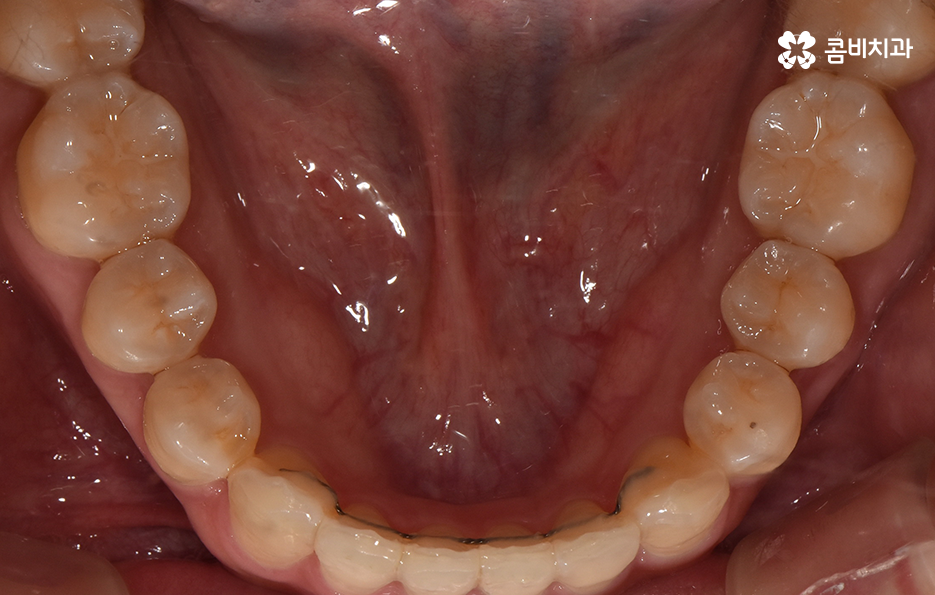

교정 치료는 크게 발치와 비발치치아교정으로 나뉠 수 있는데 비발치치아교정의 경우에는 아무래도 치아가 움직이는 양도 적고 그에 따라 교정 기간도 짧은 편에 해당되고 있어요.

교정을 하게 되면 아무래도 치아와 잇몸이 함께 움직이기 때문에 어느정도는 잇몸이 약해질 가능성이 있는데 비발치치아교정의 경우에는 치아의 이동이 큰 편은 아니기 때문에 발치교정에 비해서는 잇몸이 약해지는 정도 및 확률이 줄어들 수 있어요

반면에 발치교정의 경우에는 최소 1년 6개월 ~ 2년 이상의 교정 기간이 소요되며 치아가 빠진 공간에 나머지 치아들이 메우면서 치아의 이동이 비발치치아교정에 비해 많기 때문에 그에 따라 치아는 물론 치조골의 이동도 감안해야 하므로 치료 기간도 더 오래 걸리고 잇몸도 좀더 약해질 수 있는 확률이 발치교정에 비해서는 높은 편으로 볼 수 있는데요.

이러한 비교는 기본적으로 치아 이동의 정도 차이로 인해 치아 뿐 아니라 치조골의 이동이 큰 만큼 확률적으로 잇몸이 약해질 가능성이 상대적으로 크다는 의미로 볼 수 있어요.

그렇기 때문에 비발치치아교정이 좋다고 생각하기 보다는 개인에 따라서는 치아의 이동 공간 확보를 충분히 하기 위해 발치가 필요한 경우도 있고 얼굴 변화나 부정교합의 개선을 위해 발치가 필수적인 경우도 있을 거예요

반면에 비발치치아교정으로도 충분히 좋은 결과를 얻을 수 있는 경우도 있을텐데 이러한 치료 과정 상의 특징과 장단점을 고려하여 자신의 치료 계획을 경험 많고 숙련된 교정 전문의와 잘 상의하실 필요가 있어요